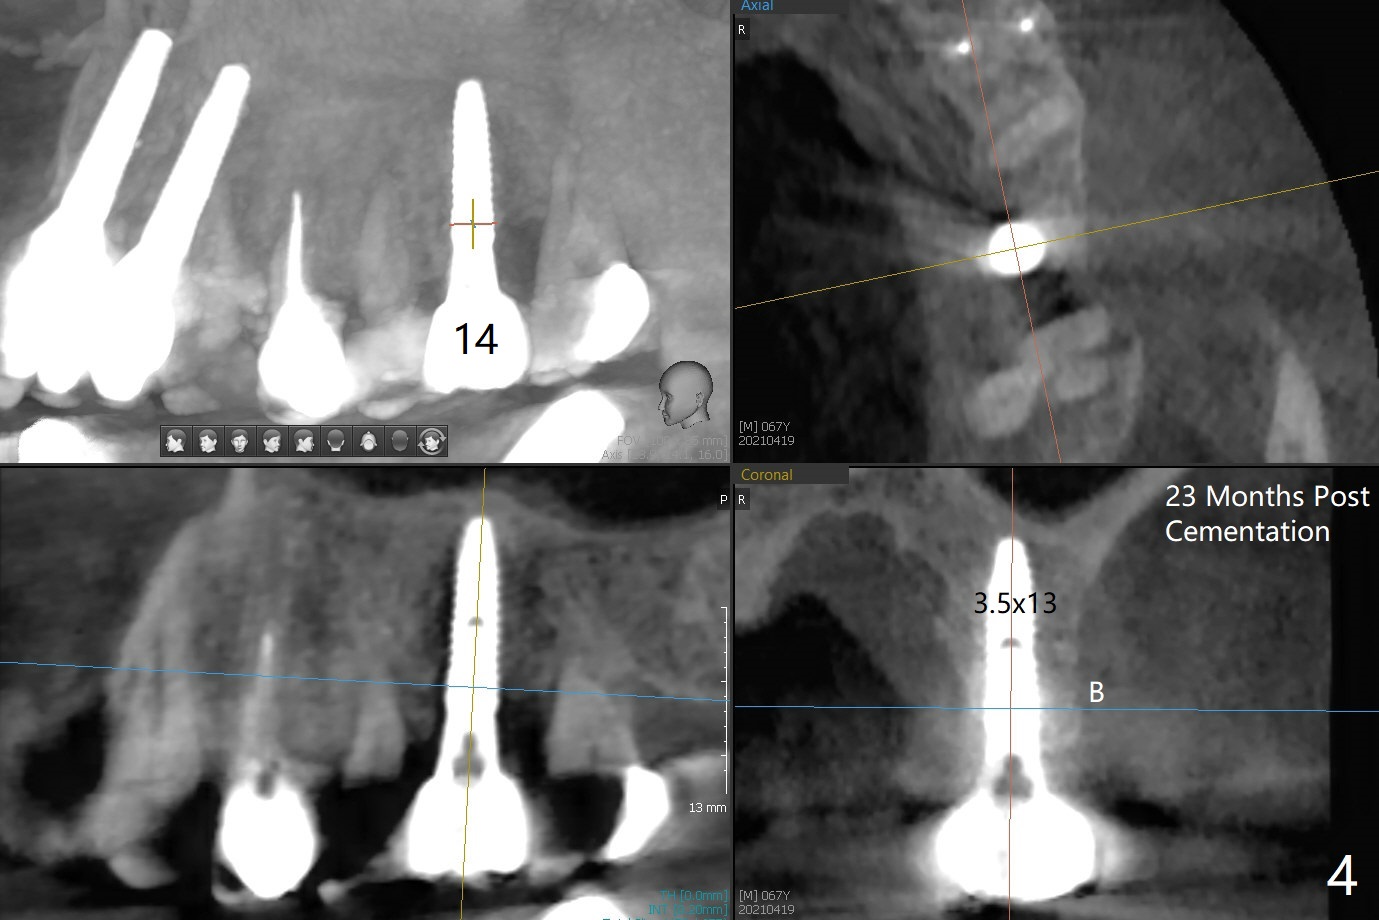

67岁男14号牙植牙牙冠粘固后两年回来处理右上(2-6)桥问题,撤除2,3单位(图一),准备种植(图二,三),3号牙牙槽嵴比较窄(图三),勉强植入4x10毫米植体,我想借助导板和它的钻头进行骨扩张,这样可以植入稍微大植体,例如4.5毫米。能不能最细钻头顺转,而再粗的钻头倒旋达到扩张目的?3号牙牙槽骨平均密度650单位。